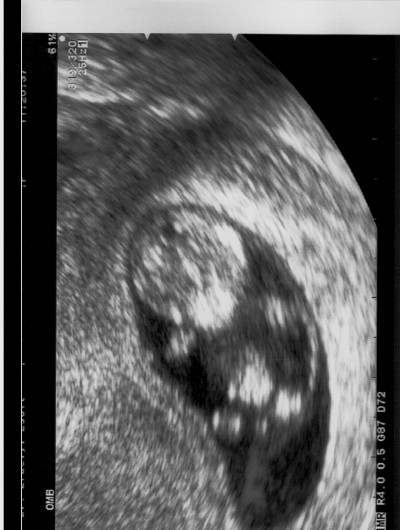

Doki nem talált semmit, sem fertőzés, sem gyulladás. Nem tudja mitől van ez, valószínű a hormonok és majd a 12 hétre talán elmúlik. Baba jól van, hatalmasat nőtt, múlt hét kedden volt 25 mm, ma meg már 38 mm . Elvileg 10+2 vagyok ma, de a doki szerint a mérete már 11 hetesnek felel meg :D . Jól belehúzott a drágám :D .

Anita, örülök h ilyen szépen nő a bébid, ez igazán megnyugtató szerintem neked is. Ki tudja ha igy halad a végén 4 kg körül fog születni.. :D

Tegnap voltunk dokinál: 29,7 mm-s a babóca. Olyan kis cuki volt. Jövő héten vérvétel a kombinált teszthez, aztán 28-án 12. heti uh. Megkérdeztem a dokit, mondta, hogy jöhet a Bendi, mert ő már nagy és nem szedi szét a rendelőt. Állítólag a kicsik rosszabbul viselik, amíg ezt a fél-3/4 órás uh-t megcsinálja.

Kinga, dejo hogy láttad a babocád, biztos nagyon édi volt, olyan jo h már ilyen fejlett a technologia, tulképp egy 3 centis baba még iszonyat pici, az uh-n meg annyira rá tudnak nagyitani, hogy egész nagynak néz ki, meg olyan igazi kis emberkének :)